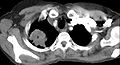

На КТ-скане визуализируется опухоль Панкоста у курящей женщины 47 лет (опухоль обозначена "Р", по гистологическим данным — немелкоклеточная карцинома правого лёгкого).

На КТ-скане визуализируется опухоль Панкоста у курящей женщины 47 лет (опухоль обозначена "Р", по гистологическим данным — немелкоклеточная карцинома правого лёгкого).